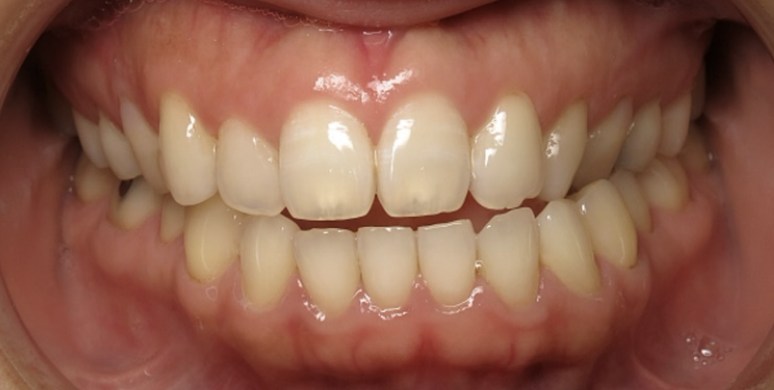

Crossbite Before and After

Before

After

A crossbite should be corrected orthodontically because it can cause asymmetric jaw growth and facial development, particularly in children, while also creating abnormal wear patterns on teeth and making them harder to clean properly.

The misalignment places uneven forces on teeth and supporting structures, potentially leading to tooth damage, bone loss, jaw muscle strain, and associated headaches or discomfort. Early treatment prevents these complications from worsening and can improve chewing function, speech clarity, and facial aesthetics.

Corrected with without surgery using invisalign